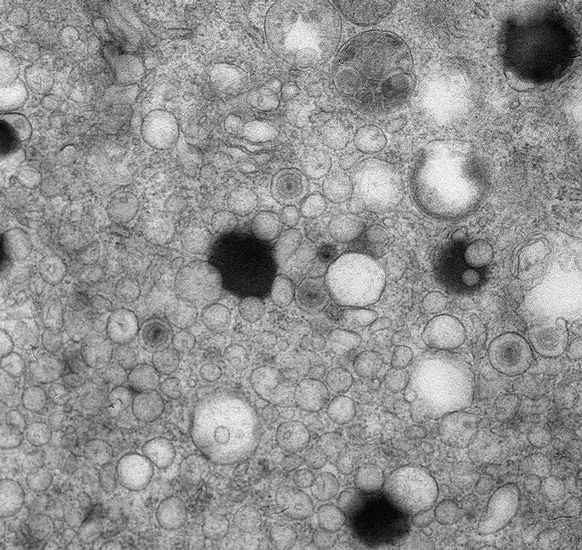

Electron microscopy image of human cytomegalovirus-infected human foreskin fibroblasts at 96 hours post-infection. Virions and dense bodies can be observed in the cytoplasm. In collaboration with Peggy Bisher from the Confocal/EM facility of the Molecular Biology Department.